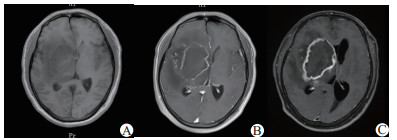

| A:8月5日MRI增强:病变未强化;B:8月12日MRI增强:病变呈环形不均匀强化,局部脑膜可见线样强化;C:8月22日MRI增强:病变呈环形强化,范围较前扩大 图 1 患者入院后MRI增强影像结果 |

1 资料与方法患者男性,39岁,以“发热头痛7 d,左侧肢体无力3 d,加重1 d”为主诉入院,7 d前受凉后出现发热体温最高40℃,伴头痛、咽痛、流涕,无寒战。3 d前出现左侧肢体麻木无力,无恶心、呕吐,头颅CT示右侧基底节区病变,脑梗死可能性大;查头颅MRI示右侧基底节区异常信号,考虑脑梗死并灶内渗血可能性大,颅脑MRA未见异常。血常规:白细胞18.43×109/L,血小板计数248×109/L;脑脊液检查:白细胞1 062×106/L,脑脊液蛋白1 765 mg/L, 在当地医院按“脑梗死/化脓性脑膜炎”给予对症治疗。1 d前患者左侧肢体无力较前加重,体温控制不佳,遂来我院。既往体健,无糖尿病等病史。入院查体:体温37.5℃,脉搏78次/min,呼吸18次/min,血压148/88 mmHg (1 mmHg=0.133 kPa),血氧饱和度99%,神志嗜睡状态,精神差,反应差,口唇无发绀,全身皮肤黏膜无黄染,浅表淋巴结不大,双侧瞳孔3.0 mm,等大等圆,对光反应灵敏,颈强直,颏下5横指,双肺呼吸音粗,未闻及干湿啰音,腹平软,腹壁反射正常,肌张力正常,左侧上下肢肌力均Ⅰ级,右侧肌力Ⅴ级,左侧躯干及肢体痛觉、触觉减退,右侧正常,左侧Babinski征阳性,右侧阴性;左侧克氏征阳性,右侧阴性。入院后查(2017-08-05)头颅MRI(图 1)示“右侧额颞叶、右侧侧脑室旁、右侧基底节、右侧大脑脚、脑桥右份占位病变,SWI提示含铁血黄素沉积,增强未强化”;行腰穿检查,脑脊液微黄,颅内压30 cmH2O(1 cmH2O=0.098 kPa),白细胞194 ×106/L,淋巴细胞70%,蛋白定量2 623.1 mg/L,糖3.4 mmol/L,氯化物128.4 mmol/L,抗酸染色阴性,墨汁染色阴性,腺苷脱氨酶8.65 ng/mL。诊断“颅内感染:化脓性脑膜炎?单纯疱疹病毒性脑炎?”,给予“美罗培南2.0 /8 h、更昔洛韦抗感染治疗”。2 d后行腰穿检查,脑脊液淡黄,颅内压27 cmH2O,白细胞550×106/L,淋巴细胞74%,蛋白定量1 798.9 mg/L,糖4.49 mmol/L,氯化物128.3 mmol/L;4 d后行结核分枝杆菌T细胞检测,抗原A 26(参考值0~5)、抗原B 13(参考值0~5);2017年8月12日行头颅MRI平扫+增强诊断(图 1)示“右侧额颞叶、右侧侧脑室旁、右侧基底节、右侧大脑脚、脑桥右份异常信号病变范围较前稍增大,病变呈环形不均匀强化、双侧额顶枕颞叶局部脑膜可见线样强化”,考虑“颅内感染:结核性脑膜炎”给予“异烟肼、利福霉素针、乙胺丁醇、吡嗪酰胺片、左氧氟沙星”抗结核治疗。2017年8月21日复查腰穿,脑脊液淡黄,颅内压40 cmH2O,白细胞78×106/L,淋巴细胞78%,蛋白定量2 446.1 mg/L,糖4.71 mmol/L,氯化物131.7 mmol/L。2017年8月22日行头颅MRI平扫+增强诊断(图 1)示“右侧额颞叶、右侧侧脑室旁、右侧基底节、右侧大脑脚、脑桥右份占位病变,边缘可见环形强化,范围较前增大,较大者病变范围56 mm×75 mm×49 mm(左右径×前后径×上下径)”。2017年8月23日神经外科行右侧颞叶基底节区脑脓肿穿刺抽吸术,术中抽出黏稠脓液约20 mL, 术后第2天患者曾出现意识障碍加重、瞳孔散大固定、呼吸急促,给予气管插管、呼吸机辅助通气、加强脱水及镇静镇痛减少应激反应降低颅内压等处理后患者神志逐渐恢复,脱呼吸机,拔除气管插管,术后病理提示“脓液真菌性炎症,形态符合毛霉菌(图 2),PAS染色阳性、六胺银染色阳性”,诊断考虑颅内毛霉菌感染,停用抗结核药物,给予“两性霉素B逐渐加量至75 mg/d, 单通路输注,输注时间10 h/d”,后转至上海华山医院感染科给予“两性霉素B联合泊沙康唑口服液治疗”,出院1年后随访患者仍服用泊沙康唑,一般情况较好,左侧上下肢肌力Ⅲ级,能在辅助下下床活动。

本文病例有以下临床特点:(1)中年男性、发病前有劳累、池塘游泳病史,池塘卫生情况差;(2)起病急、病程短,进展较迅速;(3)以发热、头痛、左侧肢体无力发病;(4)外周血白细胞计数及中性粒细胞比例明显增高,G试验阴性,GM试验阴性,脑脊液细胞数、蛋白较高,脑脊液结果提示颅内感染但不典型,明确何种颅内感染较困难,曾按照“单纯疱疹病毒性脑炎、化脓性脑膜炎、结核性脑膜炎”治疗,效果不佳;(5)影像学检查示,头颅MRI平扫加增强提示:右侧额颞叶、右侧侧脑室旁、右侧基底节、右侧大脑脚、脑桥右份病变伴出血,早期增强未强化,发病2周左右复查, 病灶呈环形强化,考虑脑脓肿可能性大;(6)外科手术,术中抽出20 mL黏稠脓液;(7)病理组织活检及染色确诊为毛霉菌感染;(8)患者因经济等原因应用两性霉素B治疗,后又加用泊沙康唑;体温恢复正常,脑脊液细胞数恢复正常,出院1年后随访患者恢复较好。